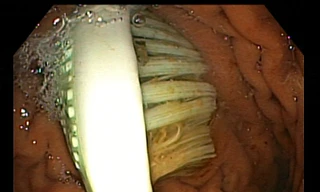

TPO - Ngày 7/9, Bệnh viện Đa khoa tỉnh Thanh Hóa cho biết, các bác sĩ vừa thực hiện thủ thuật nội soi, gắp chiếc bàn chải đánh răng trong dạ dày của nữ sinh viên Trường ĐH Hồng Đức.